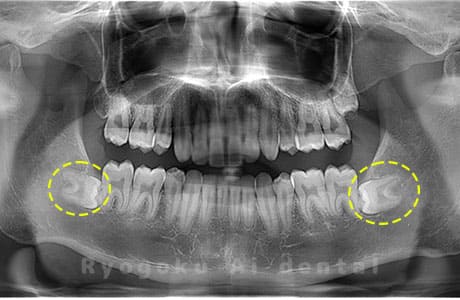

Case01

- 原因

- 水平埋伏智歯

- 治療内容

- 下顎の水平埋伏智歯を抜歯

<リスク・副作用>

手術後は痛み、腫れ、痺れなどの副作用が生じる場合があります。